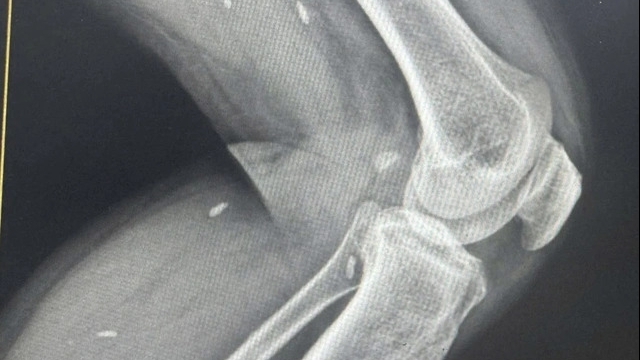

Qua chẩn đoán của các y bác sỹ, ngư dân gặp nạn hiện đang trong tình trạng nguy kịch, nhiều khả năng bị chấn thương sọ não, cần sớm tiếp cận y tế và đưa về đất liền điều trị khẩn cấp.

Tình trạng nạn nhân lúc này hết sức nguy với đa chấn thương vùng đầu, vết thương hở, chảy nhiều máu. Sau khi trải qua ca cấp cứu tại chỗ để xử lý vết thương và ổn định tình trạng, nạn nhân được đưa lên tàu SAR 412 để tiếp tục được chăm sóc tích cực và khẩn trương đưa về đất liền.